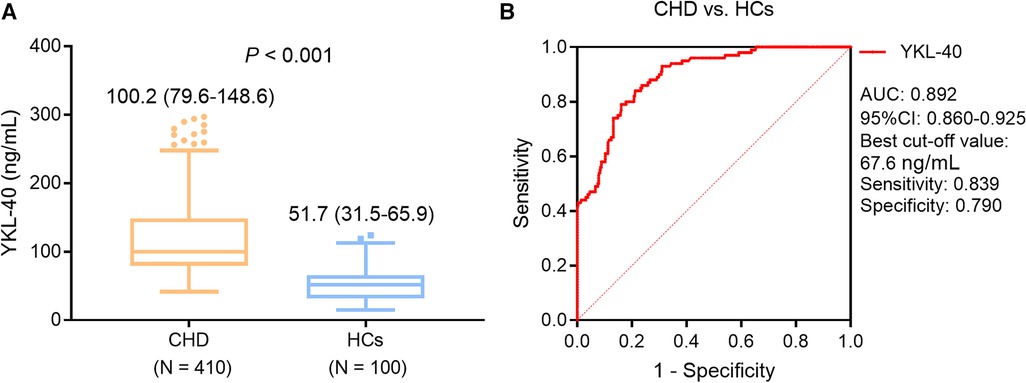

Current Diagnosis & Treatment Cardiology, Sixth Edition, Frontiers | Serum YKL-40 in coronary heart disease: linkage,

Frontiers | Serum YKL-40 in coronary heart disease: linkage, K76.81 Hepatopulmonary syndrome - ICD-10 Code, in K70-K77,自宅から出てきました。興味ある方宜しくお願いします。